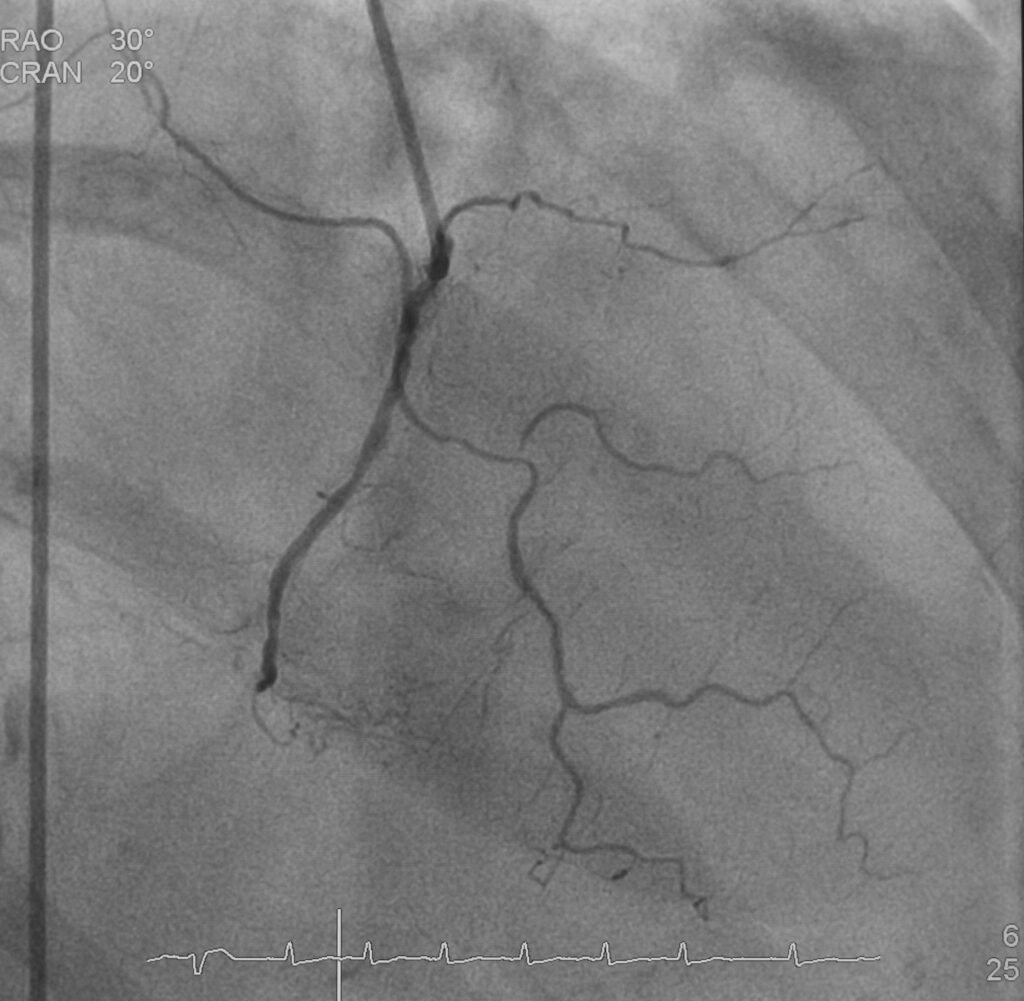

At Northern Heart Hospital Penang, advances in interventional cardiology are reshaping what it means to live with severe coronary disease. Conditions once labelled as untreatable or too risky are now approached with confidence, precision, and patient-centred care. Among these conditions is Chronic Total Occlusion (CTO), a complete blockage of a coronary artery that has been present for months or even years.

Chronic Total Occlusion is not just another type of coronary artery disease. The plaque involved is usually hard, calcified, and resistant to standard angioplasty techniques. The blockage often lacks a clear entry point, making it difficult for guidewires to cross. The anatomy can be unpredictable, and the risk of complications is higher if procedures are not performed with advanced expertise.

Treating CTO requires more than routine angioplasty skills. It demands deep anatomical understanding, specialised equipment, advanced imaging, and the ability to adapt strategies in real time. This is where Complex High Risk Indicated Procedures (CHIP), come into play.

The evolution of CHIP has transformed how cardiologists approach complex cases. Advanced guidewires, microcatheters, intravascular imaging, and refined access techniques now allow operators to navigate blockages that were once impossible to cross. Techniques such as antegrade and retrograde approaches, dissection and re-entry strategies, and meticulous imaging guidance have improved success rates while maintaining safety.